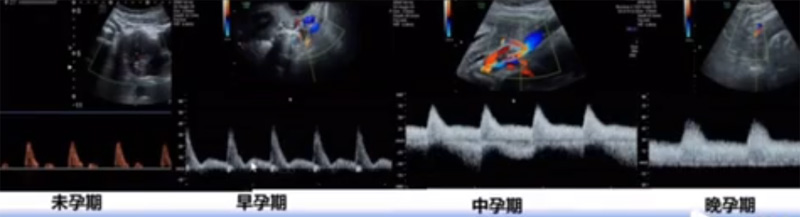

位于輸卵管的后下方,子宮兩側(cè)的后上方;借卵巢系膜與子宮闊韌帶后層相連。正常成人卵巢約4x3x2cm,跟睪丸的數(shù)值差不多,都是性器官,絕經(jīng)后卵巢萎縮變小、變硬。所以絕經(jīng)后婦女很難找到卵巢,主要功能:生殖和內(nèi)分泌功能分泌性激素。女性的第二性征。女性內(nèi)生殖器的血管分布,動脈有子宮動脈,卵巢動脈,陰道動脈,陰部內(nèi)動脈。靜脈它是與動脈伴行。重要了解的是子宮動脈,子宮動脈是髂內(nèi)動脈前干的重要分支,妊娠時候血流速度會增加的,為無創(chuàng)性檢查胎盤血管阻力的方法。未孕期頻譜為高阻力低舒張波形;正常妊娠時血流速度增加,血流阻力下降。